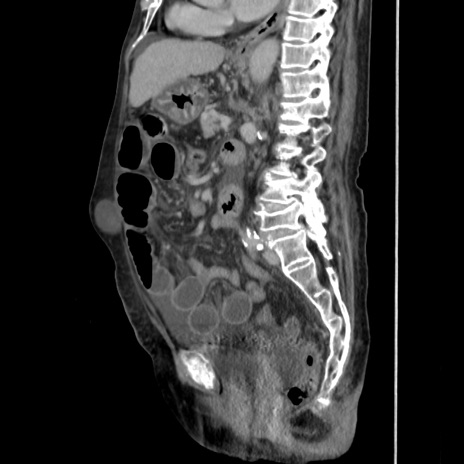

症例31(矢状断像)

【症例】80歳代 女性

【主訴】腹部膨満感

【現病歴】他院にて肝硬変にてフォロー中。1週間前から便秘、腹部膨満感、臍部腫瘤あり受診となる。

【既往歴】肝硬変

【身体所見】腹部膨隆あり、皮膚変化なし、疼痛なし。

【データ】WBC 4600、CRP 0.25